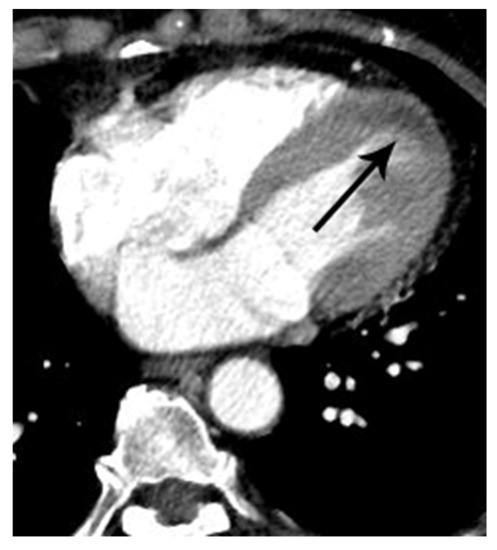

Figure 4.

False negative diagnosis of acute myocardial infarction on non-gated chest CT in a 67-year-old female with a small acute myocardial infarction. (A) Equivocal MPD (CT score of 1 for myocardial perfusion defect (MPD)) (arrow) was noted in the basal lateral segment of the left ventricle on an axial image. (B) Subsequent coronary angiography showed total occlusion (arrow) of the posterolateral branch of the right coronary artery, suggesting a culprit lesion. Note that it was difficult to differentiate true MPD from artifacts in this case.